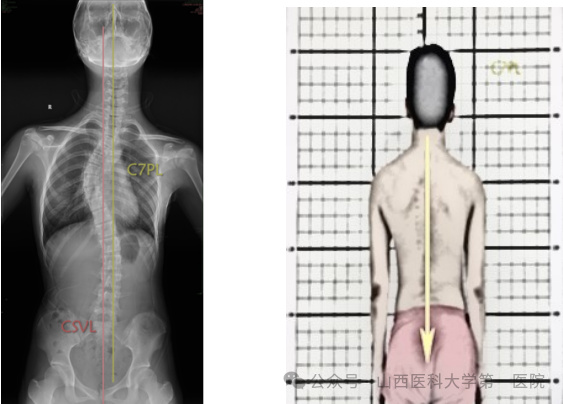

4. C7垂线(C7PL)

C7垂线是C7椎体中心垂直向下的直线,与X线片垂直边缘平行。通过测量C7垂直线与S1(CSVL)中心垂线之间的横向距离,可以确定冠状面的平衡。C7PL-CSVL代表C7PL和CSVL的水平间距。C7PL位于CSVL右侧为正值,左侧为负值,C7PL-CSVL>2cm定义为冠状面失衡。